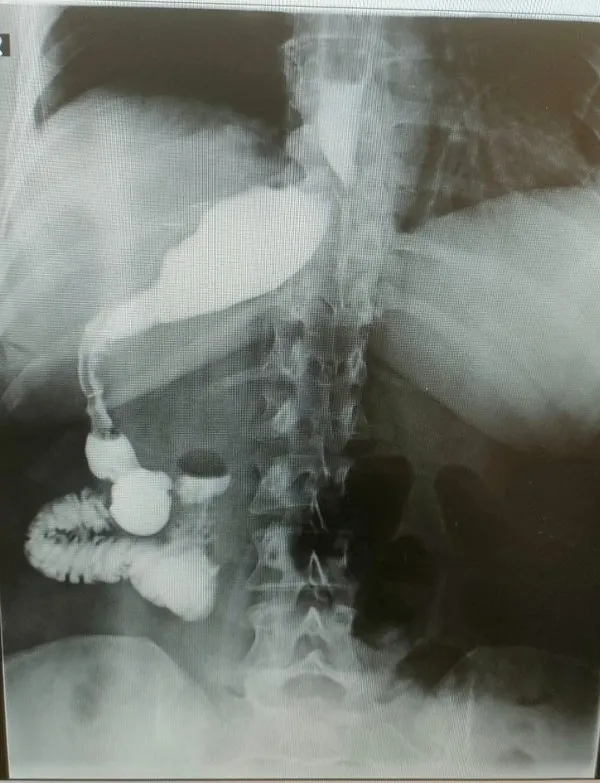

Ameliyatı gerçekleştiren Genel Cerrahi Bölüm Başkanı Prof. Dr. Alihan Gürkan, yaşadıkları şaşkınlığı şu sözlerle dile getirdi: “Çok yapılan bu operasyonlar içerisinde hastanın değişik bir anomalisi vardı. 100 binde bir görüldüğü söyleniyor. Organların hepsi ters olabiliyor. Bu daha sık görülen bir şey ama bu hastada bütün organlar yerli yerinde ama sadece mide sağ tarafa kaymış. Yani karaciğerin arkasına gitmiş. Operasyona başladığımızda mideyi bulamadık. Karaciğeri kaldırınca mideyi sağ tarafta gördük. Bu çok nadir bir durum. 2023 yılı verilerine göre, böyle bir tüp mide ameliyatı dünyada yalnızca 50 kişiye uygulanmış. Biz de bu vakayı başarıyla gerçekleştirdik. Teknik açıdan bizi zorlayan ancak deneyimimizi artıran bir ameliyat oldu”.

Prof. Dr. Gürkan, ameliyatın detaylarına değinerek, “Tüp mide operasyonunun ayna görüntüsünü yaptık. Normalde sol tarafta yaptığımız obezite ameliyatını bu hastada sağ tarafta gerçekleştirdik. Midenin karaciğerin arkasında olması ameliyat süresini 15 dakika uzattı ve toplamda 1 saat sürdü. Bizim için de hoş bir tesadüf oldu” diye konuştu.